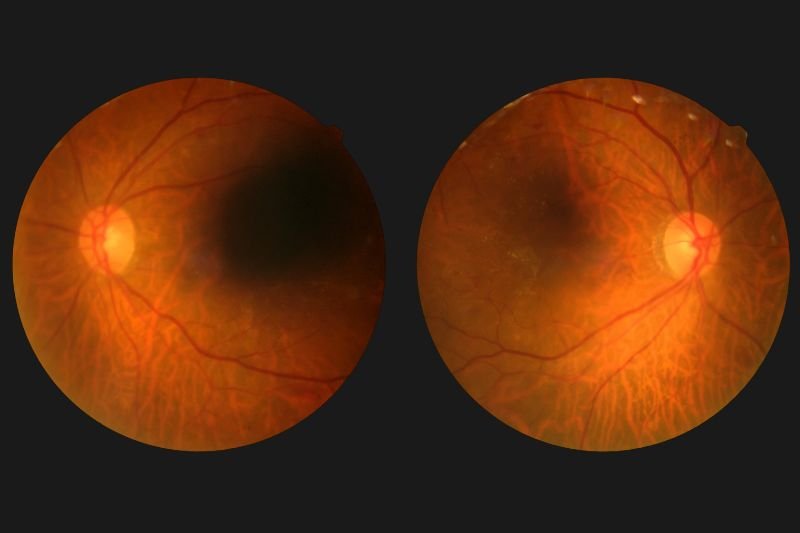

Diabetic Retinopathy Screening

Diabetic retinopathy screening detects eye damage early, protecting against blindness.